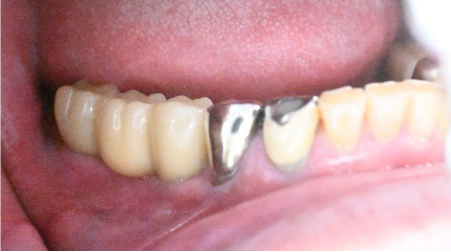

After

▼インプラント埋入後